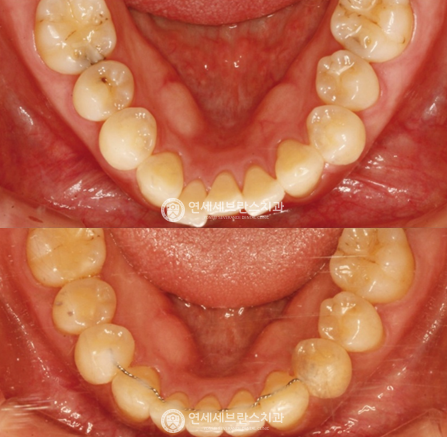

03

전악 임플란트

치아가 하나도 없거나 심각한 구강질환을 앓고 있어도

전악 보철을 제작, 임플란트를 치조골에 식립해

기능적, 심미적으로 자연치아와 가장 유사한 수준으로 재현이 가능합니다.